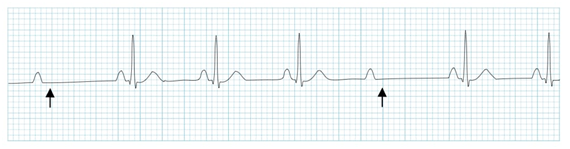

(3)心电图

表现为一段较长时间内无P波及QRS波,其长间期与正常窦性的PP间期之间无倍数关系,长间期后可见交界区或室性逸搏性心律。

二度I型房室传导阻滞的典型心电图表现,PR间期逐渐延长,而后出现QRS波脱落